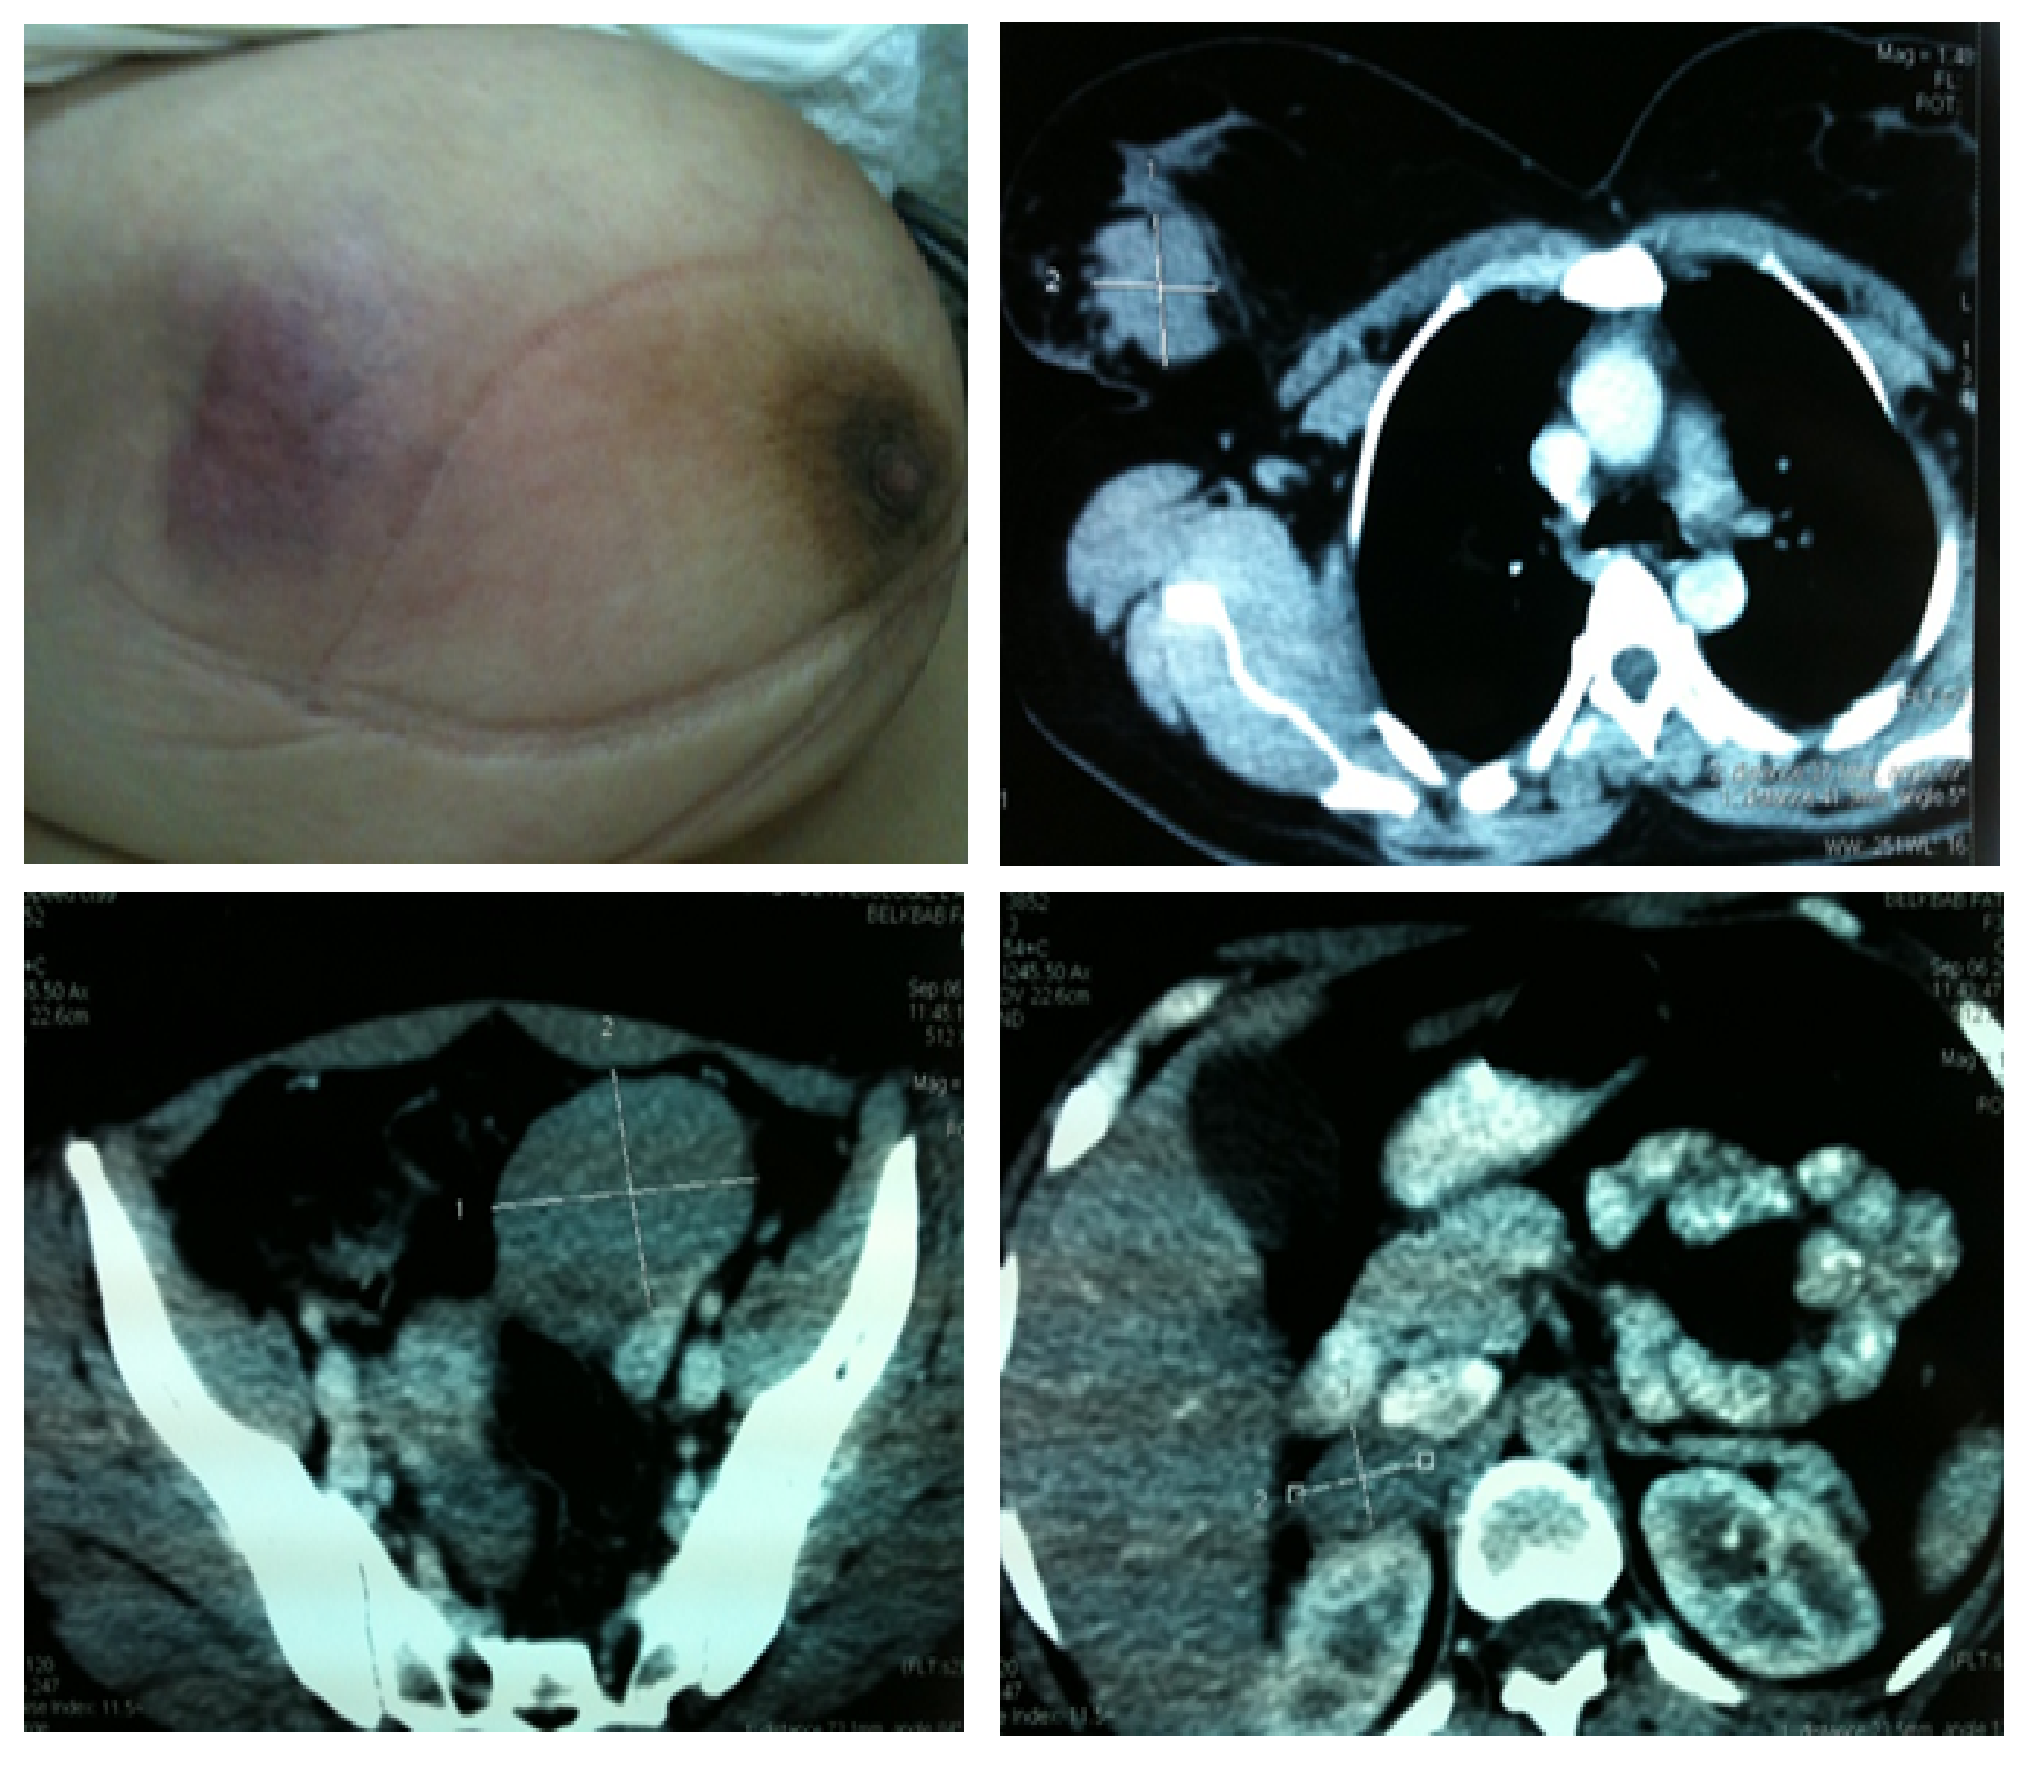

Open AccessCase Report

CHOP-treated Mammary Non-hodgkin's Malignant Lymphoma in a Female Patient with HIV + On Retroviral Treatment - Case Report

K. El Bakraoui, I. El Ghissassi, S. Boutayeb, H. Mrabet, H. Errihani

International Journal of Innovative Research in Medical Science·May 10, 2019